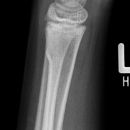

distale Radiusfraktur

distale Radius-Ulnafraktur mit Palmarabkippung

distaler Radiustrümmer Frykman VIII